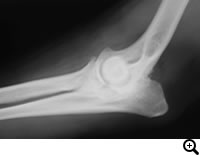

肘関節形成不全症 / FCP(内側鈎状突起分離症)

肘関節形成不全症とは

肘関節形成不全とはFCP(内側鈎状突起分離症)、UAP(肘突起分離症)、OCD(上腕骨内顆の離断性骨軟骨症)、肘関節不一致の4つの疾患が複合した肘関節疾患です。単独でみられる場合もあれば、併発して見られる場合もあります。

FCP(内側鈎状突起分離症)とは

肘関節形成不全症のうちFCPは、尺骨の内側鈎状突起の癒合障害により、尺骨から浮き上がった骨片によって関節軟骨の損傷が起こり、痛みが生じる病気です。

診断

レントゲン検査、関節鏡検査

治療

関節鏡視下で尺骨から浮き上がった骨片を切除する等の治療をおこないます。大型犬の成長期の跛行は消炎鎮痛剤等による対症療法ですませず、跛行原因の早期診断、早期治療が重要です。